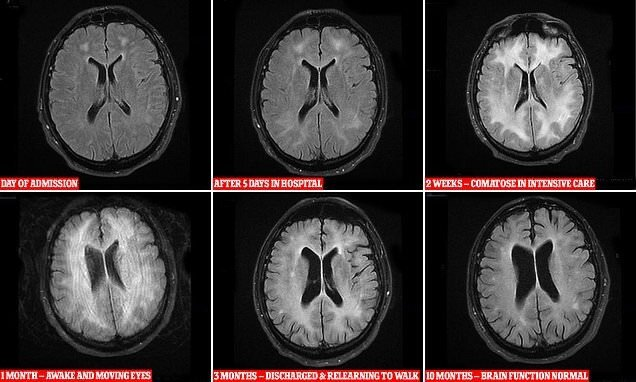

Врачам удалось запечатлеть изменения в головном мозге наркомана, употребляющего ПАВ